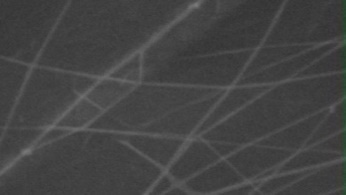

Morphology analysis was adapted from Aytac et al. (2019) [38]. The SEM analysis was conducted to detect electrospun nanofibers' fibre shape and diameter. The electrospun nanofibres from 18 runs were investigated individually by SEM (FEI, quanta 450, Czech). Images revealed the morphology of resultant nanofibers and measured their diameters in nanometres. The average number of records was calculated using a standard deviation estimation. The setting of the SEM machine was conducted on voltage 25.00 kv, magnification 23624 and width (8.3-9.3 mm).

Results of the SEM analysis are listed in table 2, with a wide range of fibre diameters starting from 87.2 nm (run 13) to 2500 nm (run 18). Run 18 did not produce true nanofibers due to the deficient concentration of PVA. The statistical analysis revealed that the effect of each polymer (factor) on the diameter size of the electrospun nanofiber was vast. Therefore, there is a correlation between factors A, B and C and fibre diameter as expressed in equation 5.

Fig. 3: Nanofibres SEM images with nanofiber diameter frequencies. The PVA, PEO and HPMC were symbolised as V, E and P. Data are given in mean±SD, n=3

The morphology of nanofibers would be affected by device parameters such as flow rate, voltage and distance from the collector. Also, nanofibres' properties could be changed due to temperature and humidity. The bead formation appears with a low concentration of PVA (run 2) or a high concentration of PEO and HPMC (runs 6 and 11), as shown in fig. 3. Therefore, increasing PVA concentration leads to beads' disappearance and smooth fibres' formation. Nageeb El-Helaly (2021) and Silva J. A. et al. (2021) reported similar results [47, 48]. Kalluriet al.(2021)[49] studied the relationship between the fibre diameter, bead diameter and flow rate. Thus, they concluded that better fibre uniformity and bead formation were needed at a high flow rate. These results appear clearly in run two and run six and agree with Silva et al.(2021) results [50], who reported that only the concentration of PVA (≥ 15%) could produce uniform nanofibers when using the lower molecular weight of PVA (67,000). Fibre diameter of 15% PVA and more appeared to be in the range 87.11 to 252.5 nm with uniform fibres and disappearance of beads except in run 6, where the beads appear due to increasing the concentration of HPMC as highlighted by Gripet al. (2018) [46].